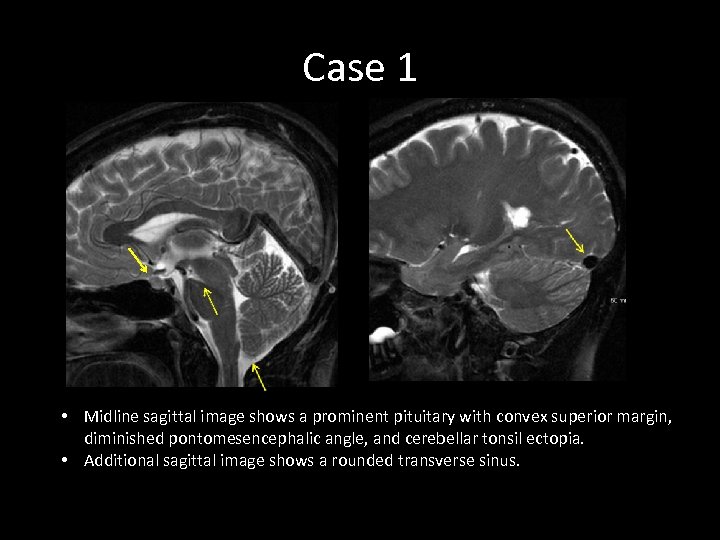

Case 1 • Midline sagittal image shows a prominent pituitary with convex superior margin, diminished pontomesencephalic angle, and cerebellar tonsil ectopia. • Additional sagittal image shows a rounded transverse sinus.

Case 1 • Midline sagittal image shows a prominent pituitary with convex superior margin, diminished pontomesencephalic angle, and cerebellar tonsil ectopia. • Additional sagittal image shows a rounded transverse sinus.